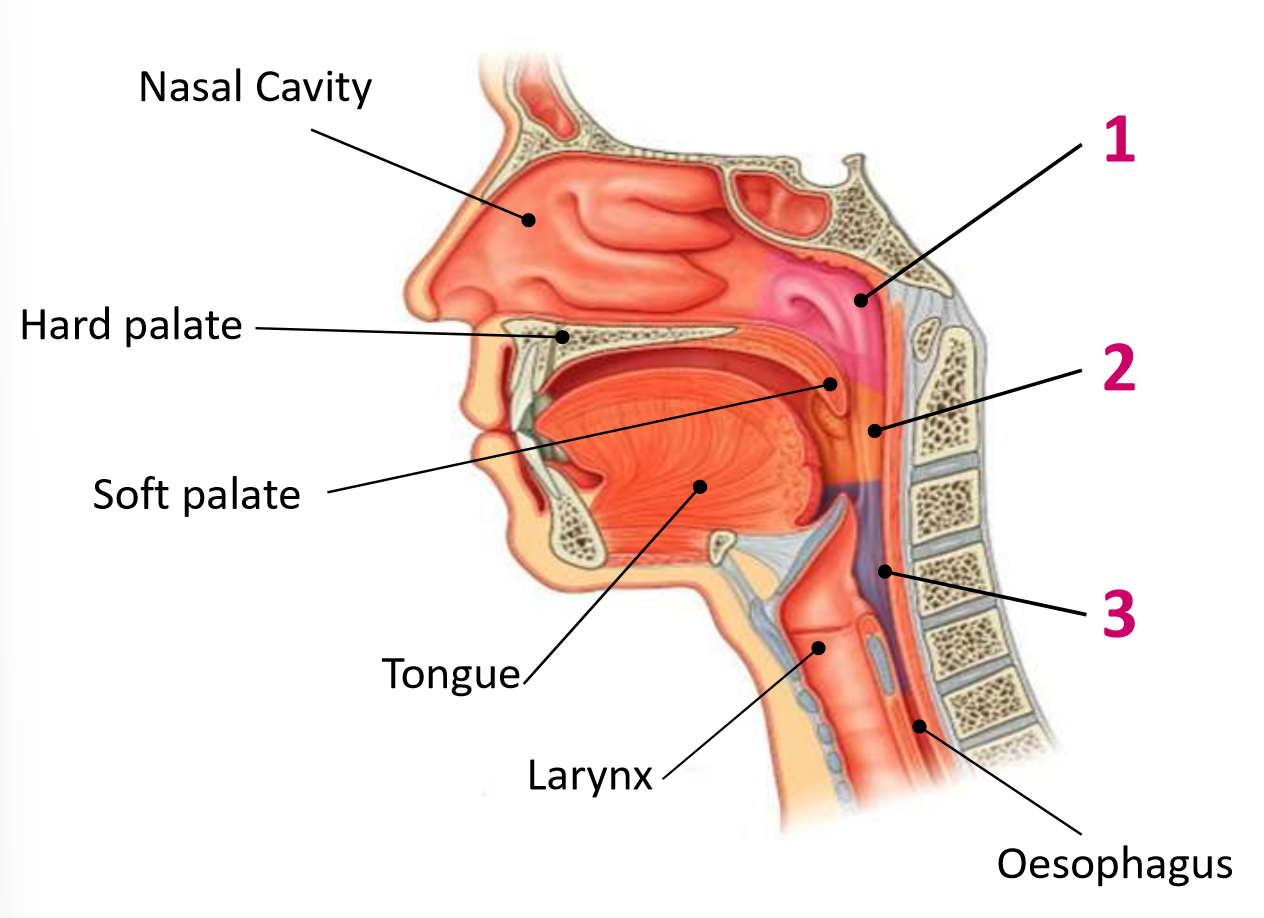

Which area of the head and neck do 1, 2, and 3 make?

pharynx

What region is 1?

nasopharynx

What region is 2?

oropharynx

What region is 3?

laryngopharynx